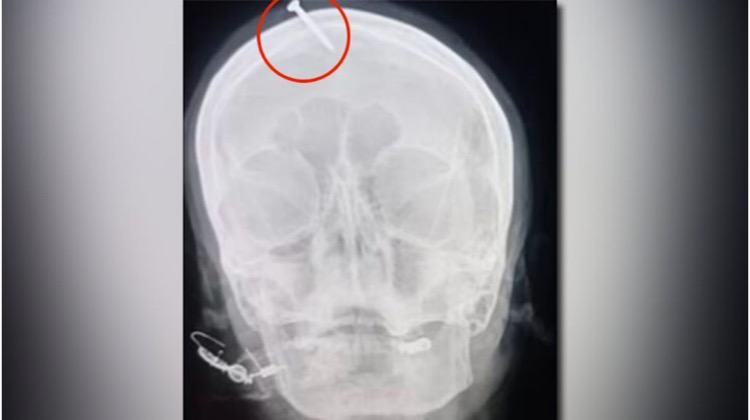

Una mujer embarazada fue atendida de emergencia en el Hospital Lady Reading, ubicado en la ciudad de Peshawar, en Pakistán, debido a que tenía incrustado en la frente un clavo de más de cinco centímetros. De acuerdo con información oficial, la señora se dejó clavar el objeto por recomendación de un curandero.

Entonces, el curandero le dijo a la mujer que se pusiera un clavo en la frente y así daría a luz a un niño. Cuando llegó al hospital, la embarazada dijo que ella lo había hecho, pero después admitió que había sido el hombre quien le había clavado el objeto. Luego contó que acudió por atención médica luego de sentir dolor y no poder quitarse el clavo ella misma.

Haider Suleman, el neurocirujano que la atendió, dijo al medio pakistaní, que la mujer resultó con una lesión grave en la cabeza, aunque el clavo afortunadamente no llegó al cerebro. Además, dijo que la ecografía que le practicaron en el hospital reveló que estaba pronta a dar a luz a la niña.